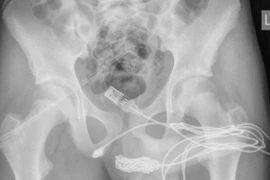

Can thiệp chỉnh sửa bộ phận sinh dục

Có rất nhiều lựa chọn khi xem xét phẫu thuật thẩm mỹ bộ phận sinh dục. Nghiên cứu trước và thăm khám, tư vấn sẽ giúp bạn và bác sĩ phẫu thuật xác định mục tiêu và lập kế hoạch để đạt được kết quả tốt nhất có thể.